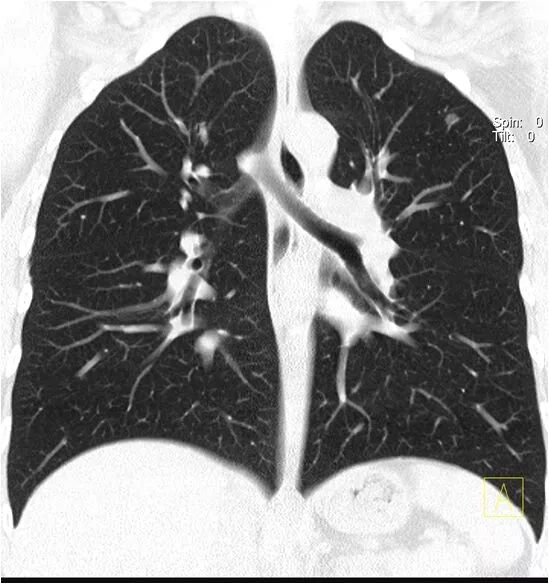

对于临床安全成像而言,SOMATOM Drive给出了新的解决方案。西门子独有的kV纯谱技术可以在一张胸片的辐射剂量下获得全肺的CT筛查图像,而Drive将这项技术扩展到了全身,所有天然对比度高的部位都可以在胸片级别的剂量下获得平扫的图像;尤其值得一提的是心肺一体化成像,使用SOMATOM Drive,可以在一次肺部平扫中,同时获得肺部肿瘤学信息和心血管的风险评估信息(双源CT提供了在一次心跳内完成心脏扫描的方法,从而实现高质量、低剂量冠脉成像)。

胸部肺动脉扫描检查,扫描时间不到1秒,可以得到清晰的肺动脉图像,避免肺静脉干扰。